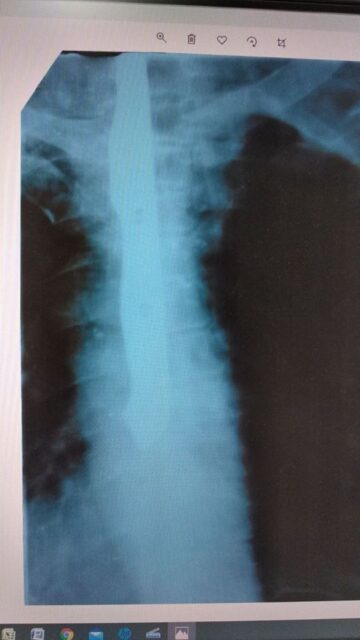

Як повідомляє Energodar NEWS, пацієнтові зробили рентген. На знімку лікарі побачили у стравоході предмет, схожий на ніж.